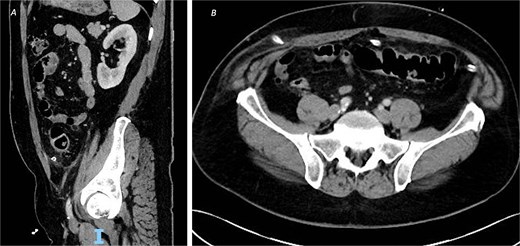

Post-operatively, the patient made a good recovery. As per local policy, he remained on intravenous antibiotics until discharge. In the immediate post-operative period, he was kept nil-by-mouth for 2 days and received total parenteral nutrition, before having his dietary intake increased after he passed flatus and opened his bowels. The patient was tolerating a normal diet by post-operative Day 5, with serial inflammatory markers also improving. A repeat CT scan on post-operative Day 8 confirmed resolution of the inflammatory changes with no evidence of leak or abscess formation (Fig. 2), and his intra-abdominal drains were subsequently removed.

CT of the abdomen and pelvic with contrast on post-operative Day 8 demonstrating resolution of the inflammatory changes with no evidence of leak or abscess formation, from (A) sagittal view and (B) axial view.